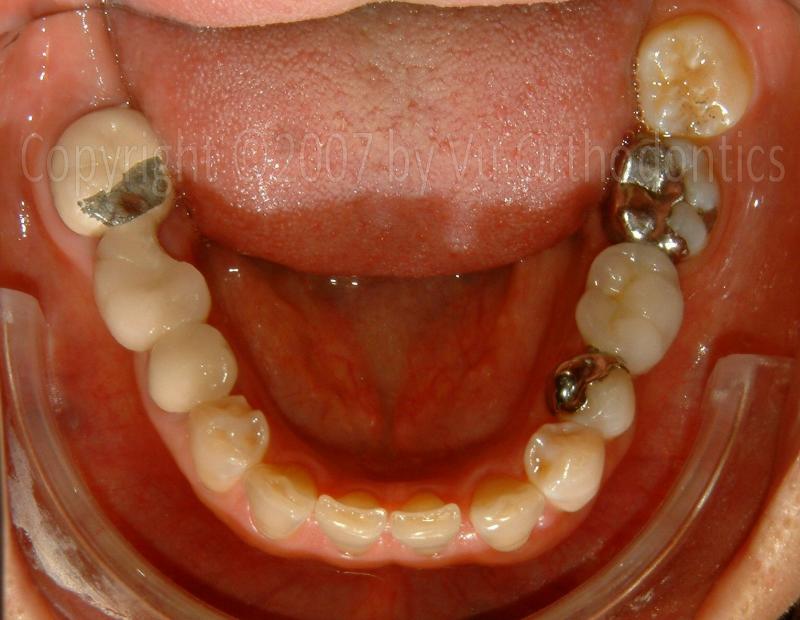

A Case that needs Free Gingival Graft (FGG)

For many patients, the posterior of the lower arch needs Free Gingival Graft (FGG) because of poor quality of keratinized mucosa. The case, infra, shows as an example.

Fig. 9. A broken 3-unit bridge (for the missing Tooth #30)